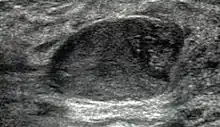

Macroscopic view of fibroadenoma of the breast

Closeup of a fibroadenoma of the breast

Macroscopic

Approximately 90% of fibroadenomas are less than 3 cm in diameter. However, these tumors have the potential to grow reaching a remarkable size, particularly in young individuals. The tumor is round or ovoid, elastic, and nodular, and has a smooth surface. The cut surface usually appears homogenous and firm, and is grey-white or tan in colour. The pericanalicular type (hard) has a whorly appearance with a complete capsule, while the intracanalicular type (soft) has an incomplete capsule.[11]